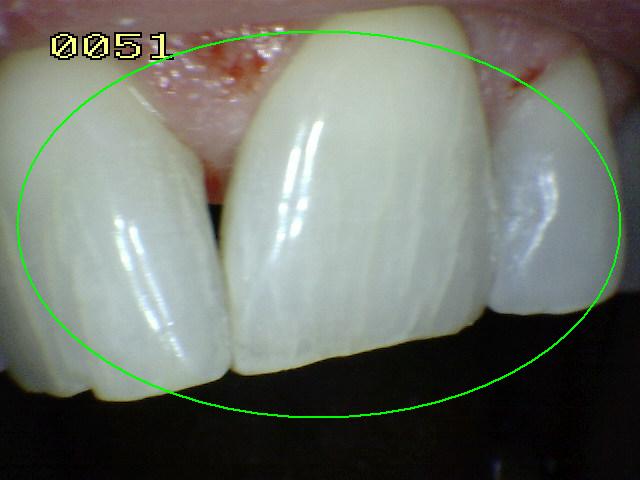

Código 3

(Caries Moderada): Ruptura

localizada del esmalte debido a caries sin dentina visible

- Una vez secadas durante aproximadamente

cinco segundos se observa una pérdida clara de la integridad

del esmalte, visto desde la dirección vestibular o lingual.

- En húmedo están presentes lesiones

blancas o decoloradas.

- En caso de duda, o para confirmar la

evaluación visual, la sonda IPC puede ser

utilizada

suavemente por la superficie para confirmar la pérdida de la

integridad de la superficie del esmalte.< 0,5 mm.